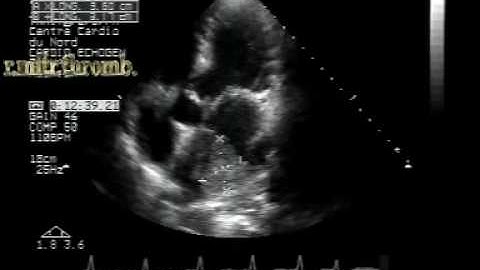

MS different aspects:left atrial appendage thrombus .TEE